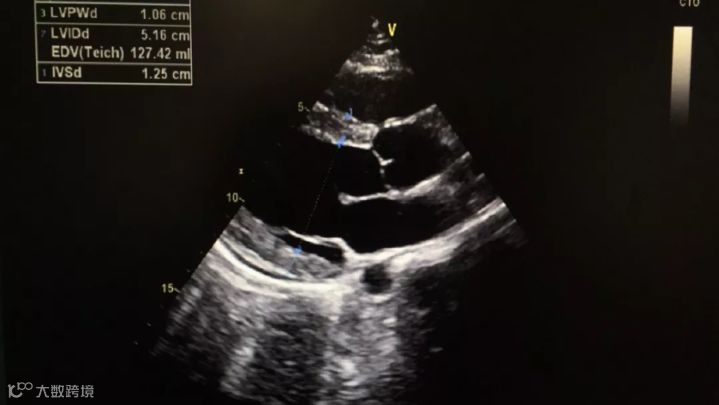

在杭州打工的父母听说儿子的事情急坏了,11月1日,小张父母将小张接到了杭州,送到浙大一院急救中心进行诊治,经过胸部CT、心电图和心脏彩超检查,发现小张的心电图ST段抬高,心肌酶谱中血清肌钙蛋白含量也高出了正常人近400倍,心肌受损情况严重。

收缩期

舒张期

在急救中心,小张进行了五天的糖皮质激素输液,并转到心内科做进一步治疗,在浙大一院经过十天的抗生素输液治疗和营养心肌的药物辅助,目前小张的心电图、心超、心脏功能等已恢复正常。